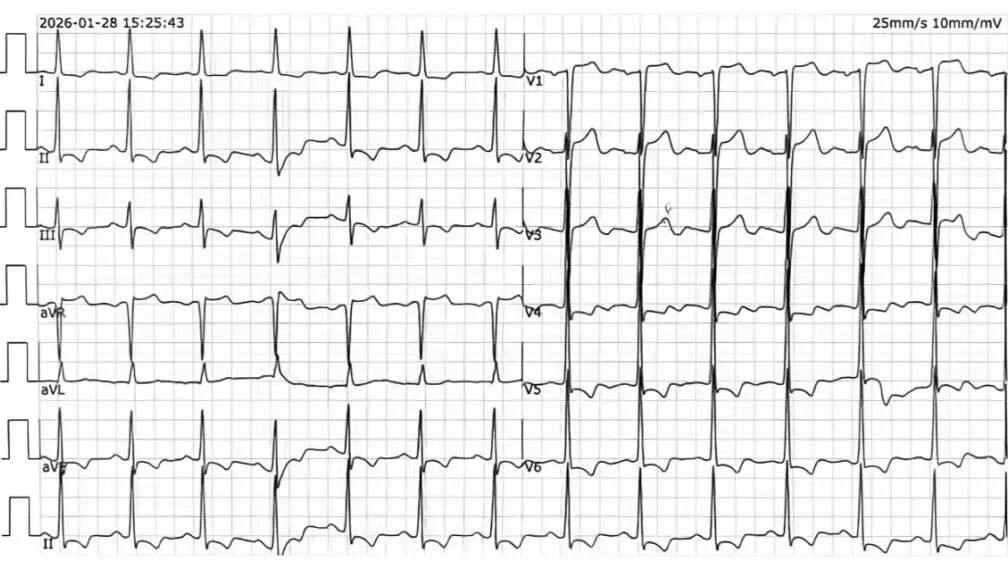

心电图示: